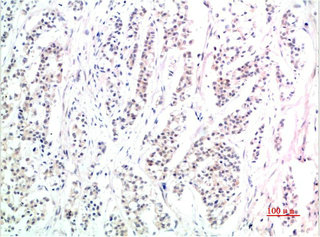

• Immunohistochemical analysis of paraffin-embedded Human Skin Tissue using Phospho-Smad3 (S425) Mouse mAb diluted at 1:200

• Immunohistochemical analysis of paraffin-embedded Human Stomach Carcinoma Tissue using Phospho-Smad3 (S425) Mouse mAb diluted at 1:200